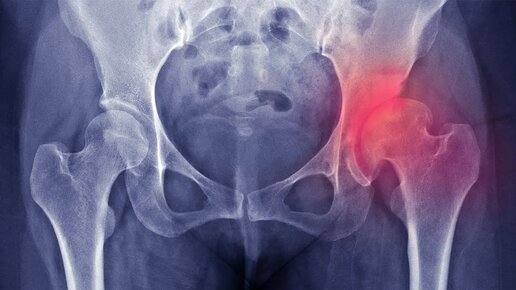

Вы собираетесь выйти на улицу, но первый шаг отзывается острой болью в паху или сбоку бедра. Вы осторожно опираетесь на стену, делаете ещё один шаг — чуть легче, но дискомфорт остаётся. Через пару минут, кажется, проходит. Но к вечеру всё возвращается. Со временем вы начинаете избегать длительных прогулок, лестниц, даже походов в магазин. Ваш круг общения сужается, активность падает, а настроение — вместе с ней. Это может быть не просто «возрастное» недомогание, а коксартроз — постепенное разрушение тазобедренного сустава...

Коксартроз